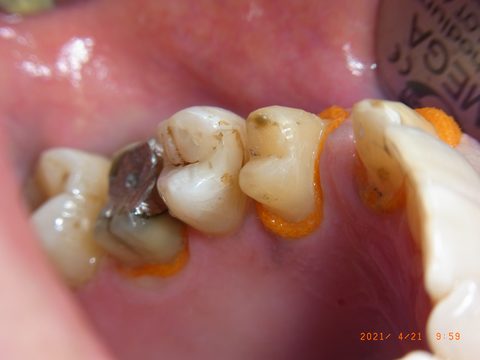

Retraktionsfaden auch im Seitenzahnbereich. Die Abdruckspritze steht bereit, um unmittelbar nach Fadenentnahme mit der Zweitabformung zu beginnen.

Ich vermute, daß durch den durch die Foliendicke definierten Spalt eine gute Führung und kräftige Strömung des zweitabformenden Materials entstehen. Ich bekomme jedenfalls in der Routine so tiefe Sulcusabformungen und fehlerfreie, scharfe Abdrücke wie selten zuvor.

Detail der fertigen Zweitabformung: Die Stümpfe sind scharf und tief erfasst, Sulcusränder deutlich sichtbar – ohne Fahnen, ohne Lufteinschlüsse.

Gesamtansicht der fertigen Zweitabformung: vollständige Erfassung des Oberkiefers. Die beiden unabhängigen Abformungen erlauben dem Labor das Umsetzen zwischen den Modellen und decken Abformfehler frühzeitig auf.